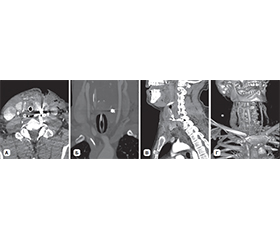

Актуальність. У статті проведений аналіз обстеження та лікування вогнепальних поранень шиї з ушкодженням щитоподібної залози (ЩЗ) за останні три роки в умовах Військово-медичного клінічного центру Північного регіону КМС ЗСУ. Мета: розробка та впровадження класифікації вогнепальних поранень шиї з ушкодженням ЩЗ. Матеріали та методи. Усі пацієнти були чоловічої статі, мали вогнепальні осколкові поранення шиї. Виконані лабораторні дослідження, ультразвукове дослідження шиї, мультиспіральна комп’ютерна томографія голови, шиї, органів грудної клітки та черевної порожнини, таза з контрастуванням та без, рентгенографічні дослідження органів грудної клітки та черевної порожнини, відеоезофагогастродуоденоскопія та відеобронхоскопія, електрокардіографія. Результати. Частота вогнепальних поранень шиї з ушкодженням ЩЗ за роками (2022, 2023, 2024) становить 5,2; 9,3; 8,7 %. Частота ушкоджень ЩЗ вогнепального походження за останні 2 роки збільшилась, що пов’язано із застосуванням противником дронів. У середньому, за нашими даними, ушкодження ЩЗ серед вогнепальних поранень шиї з ушкодженням порожнистих та паренхіматозних органів становить 7,5 %. Класифікація побудована на основі даних обсягу ушкодження, відповідної тактики лікування та можливої замісної гормональної терапії (якщо не було її призначено до поранення), які розподілені за класами. За обсягом ушкодження розподіл такий: І клас — забій ЩЗ, ІІ клас — поверхневе ушкодження (до 0,5 см глибиною), ІІІ клас — глибоке ушкодження, до 50 % частки, ІV клас — глибоке ушкодження, більше ніж 50 % частки, V клас — розтрощення ЩЗ. За класами частота ушкоджень ЩЗ розподілена: ІІ клас — 41,4 %, І клас — 34,3 %, ІІІ клас, клиноподібна або крайова резекція, резекція полюса або перешийка — 20,7 %, ІV клас, гемітиреоїдектомія — 3,4 %, V клас, тиреоїдектомія — 0 %. Усі поранення були осколковими. Ізольованих поранень ЩЗ не визначалось, що пов’язано з її анатомічним розташуванням. За тактикою лікування: ІІ клас, первинна хірургічна обробка рани — 41,4 %, І клас, консервативна терапія — 34,3 %, ІІІ клас — 20,7 %, ІV клас — 3,4 %, V клас — 0 %. Замісна гормональна терапія була в подальшому призначена пацієнтам з ІV класом. Середній термін лікування становив 10,2 ± 1,3 доби. Висновки. Вогнепальні поранення шиї з ушкодженням ЩЗ є рідкісною патологією. Запропонована класифікація дозволяє визначитися з лікувальною тактикою та прогнозом. Анатомічні та фізіологічні особливості ЩЗ повинні братися до уваги при оперативному лікуванні ЩЗ при її ушкодженні. Оперативні втручання з приводу ушкоджень ЩЗ слід проводити на рівні ROLE IV за наявності відповідних фахівців та обладнання.

Background. The article analyzes the examination and treatment of gunshot wounds of the neck with damage to the thyroid gland (TG) over the past 3 years in the conditions of the Military Medical Clinical Center of the Northern Region of the Medical Forces Command. The aim is to develop and implement a classification of gunshot wounds of the neck with damage to the TG. Materials and methods. All patients were male, had gunshot shrapnel wounds of the neck. Laboratory tests were performed, as well as ultrasound examination of the neck, multispiral computed tomography of the head, neck, chest and abdominal organs, pelvis with and without contrast, X-ray examinations of the chest and abdominal organs, video esophagogastroduodenoscopy and vi­deo bronchoscopy, electrocardiography. Results. The frequency of gunshot wounds to the neck with damage to the TG by years (2022, 2023, 2024) is 5.2, 9.3, 8.7 %. It has increased over the past 2 years, which is associated with the use of drones by the enemy. On average, according to our data, thyroid injuries among gunshot wounds to the neck with damage to hollow and parenchymal organs account for 7.5 %. The classification is based on the extent of the injury, appropriate treatment, and possible hormone replacement therapy (when it was not prescribed before the injury), which are distributed by class. The distribution by the extent of damage is as follows: сlass I — contusion of the TG, сlass II — superficial damage (up to 0.5 cm deep), сlass III — deep damage, up to 50 % of the lobe, сlass IV — deep damage, more than 50 % of the lobe, сlass V — crushing of the TG. The frequency of thyroid injuries is distributed by class: class II — 41.4 %, class I — 34.3 %, class III — wedge or marginal resection, pole or isthmus resection: 20.7 %, class IV — hemithyroidectomy: 3.4 %, class V — thyroidectomy: 0 %. All injuries were shrapnel. Isolated injuries of the TG were not identified, which is associated with its anatomical location. According to treatment, class II — primary surgical wound treatment: 41.4 %, class I — conservative therapy: 34.3 %, class III — 20.7 %, class IV — 3.4 %, class V — 0 %. Hormone replacement therapy was subsequently prescribed to patients with class IV. The average duration of treatment was 10.2 ± 1.3 days. Conclusions. Gunshot wounds of the neck with damage to the TG are a rare pathology. The proposed classification allows us to determine the treatment and prognosis. The anatomical and physiological features of the TG should be taken into account during surgical treatment for thyroid injury. Surgical interventions for thyroid injuries should be performed at the Role IV with the availability of appropriate specialists and equipment.